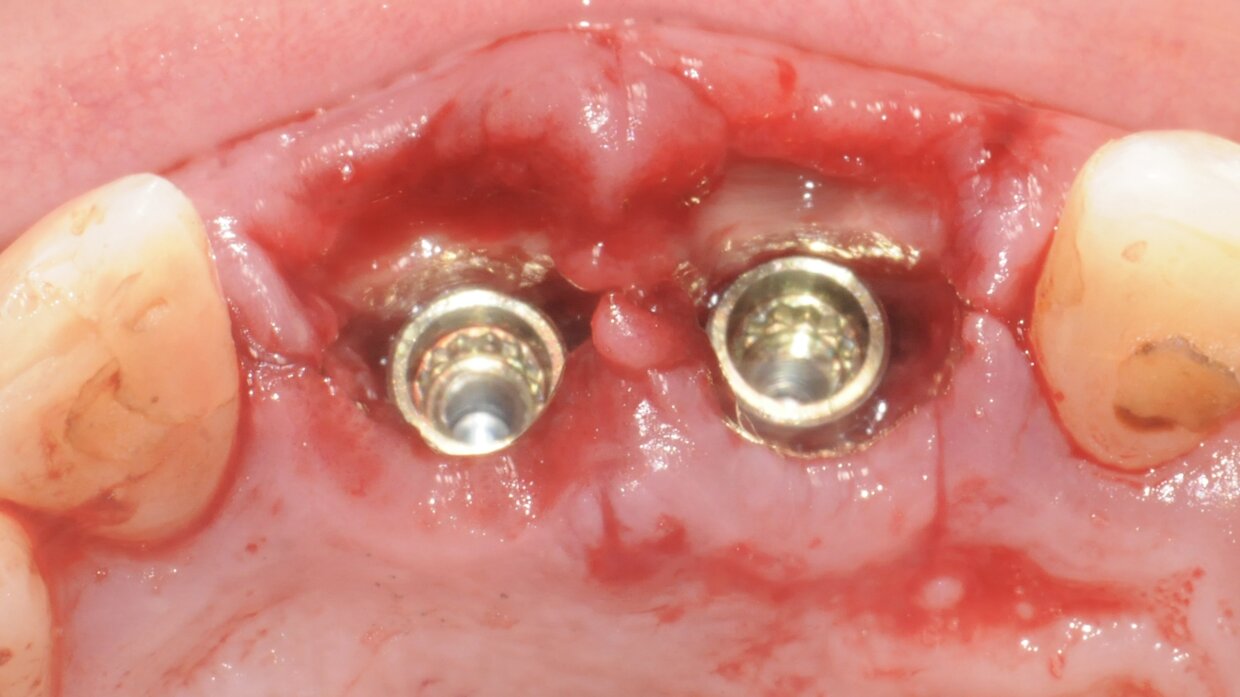

Minimamente invasivo, senza lembo chirurgico nè punti di sutura

Il posizionamento degli impianti è stato pianificato prima dell'intervento su un software dedicato. In un'unica seduta, dopo l'estrazione degli elementi dentari compromessi, sono stati immediatamente inseriti gli impianti nella posizione pianificata, grazie alla realizzazione della dima chirurgica. Per ridurre il riassorbimento osseo a lungo termine e garantire quindi una maggiore resa estetica (vista la zona d'intervento), la chirurgia è stata eseguita con una particolare tecnica denominata: Socket Shield Technique.